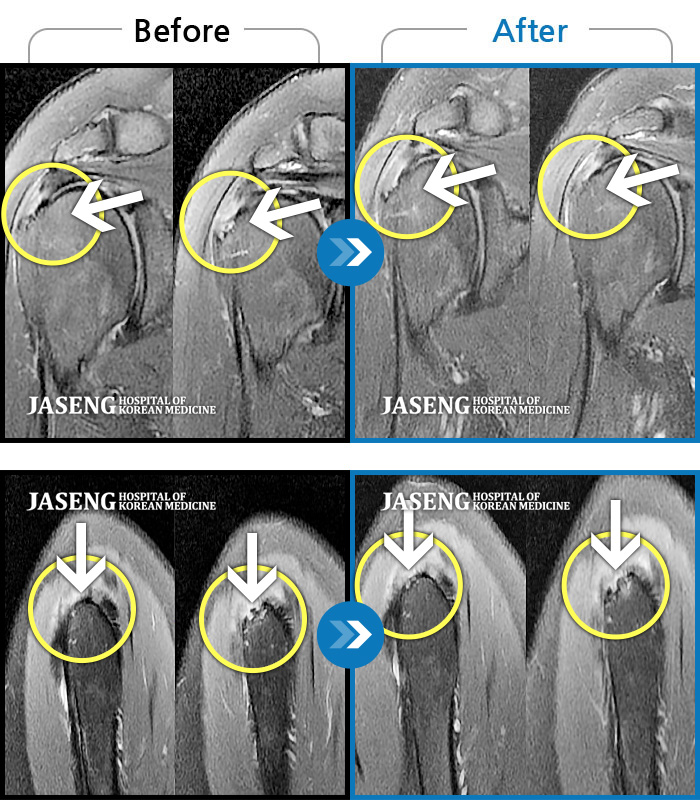

ȯںп Ǹ ǿ ԿǾ, ο ġ ۿ Ƿ ġḦ Ͻñ ٶϴ.